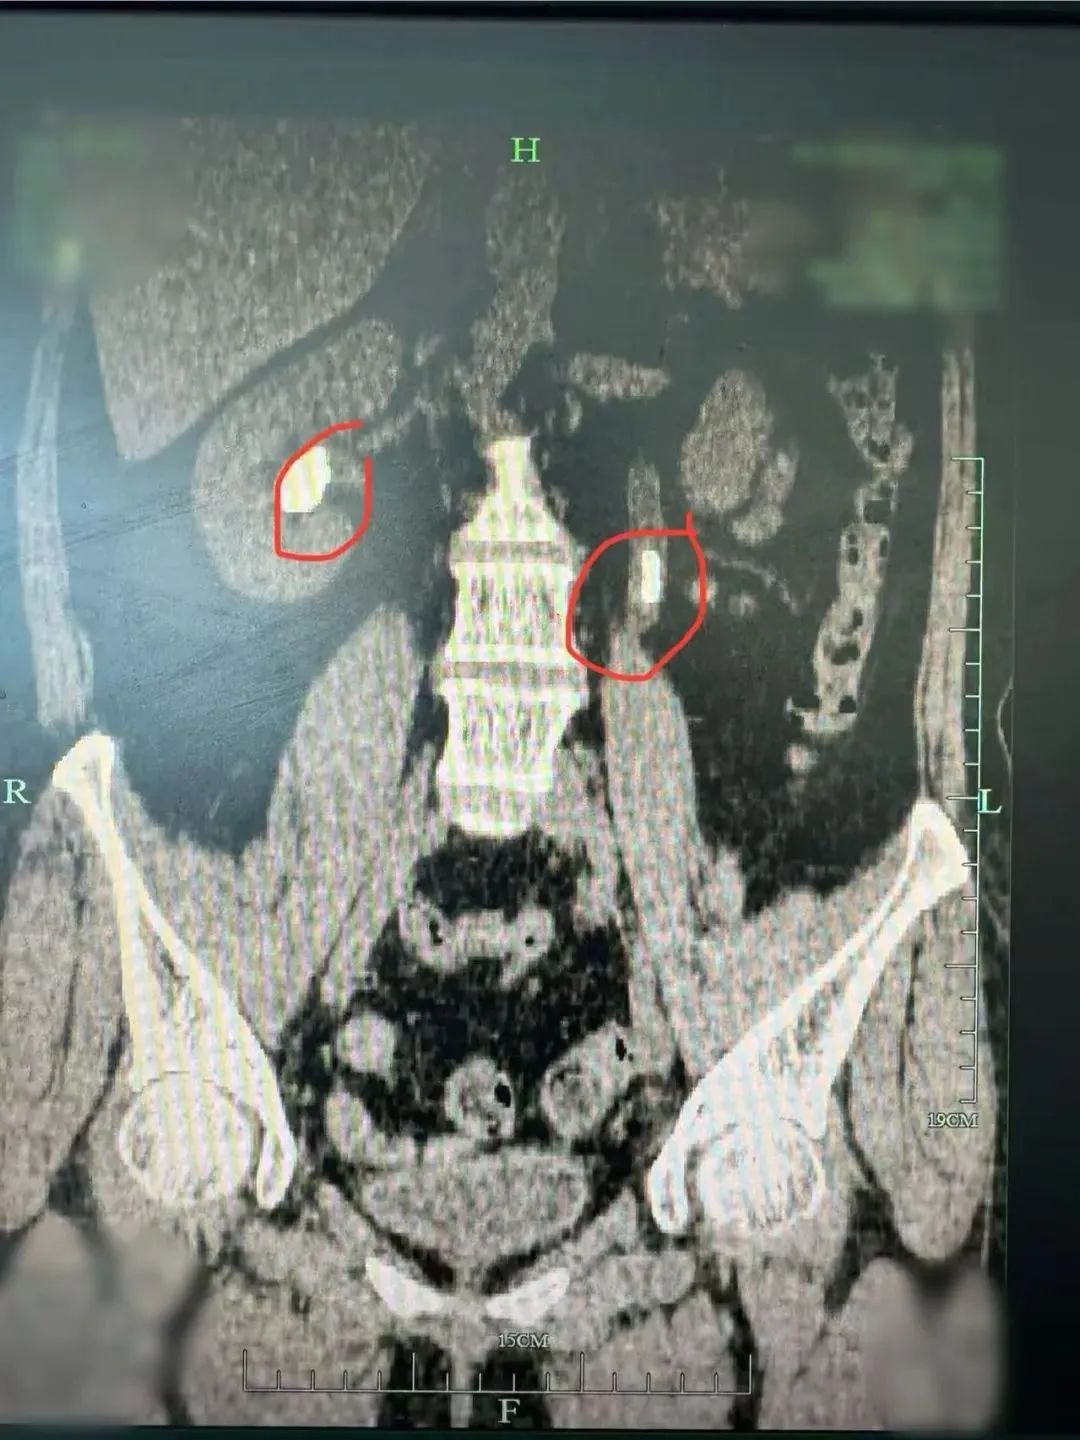

红圈内为双肾结石

1个月前,她再次来到泌尿外科主任秦勇主任医师的专家门诊,经CT检查发现她的双肾结石又发展到了不得不手术治疗的程度,内镜手术一如既往地顺利,但细心的秦勇发现她曾有过骨折和关节病变,甲状旁腺激素(PTH)也有升高,高度怀疑泌尿系统结石是由于甲状旁腺功能亢进继发引起的。可经过超声和CT检查并没有在颈部甲状旁腺发现明显异常。